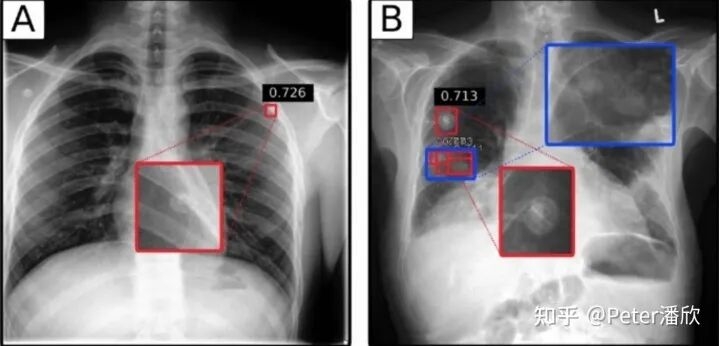

17年Brain下成立一个放射科的医疗影像团队:Radiology。由于我正好在这个领域开发模型,就帮助了这个团队的创建。

最初我们先从简单的XRay下手。我将FasterRCNN先经过CoCo的预训练,然后再几百张XRay样本上做了一些fine-tune,结果意外的好。

后来我们深入到更难的CT场景。CT是对人进行3维立体的扫描,因此对应的框需要包含长宽高。由于当时是兼岗,我简单将CT做了抽帧,转换成多张二维图片,然后通过FasterRCNN,然后再三维化。这样效果比较一般。后来一个韩国小哥实现了一个高性能的3D检测,取得了更好的效果。

AI医疗的上线是非常困难的,特别是在美国这种FDA管理比较严格的国家。当时我们找到一个场景,据说是不需要FDA Apporve的:

通常需要被诊断的Radiology数据是FIFO排队被医生诊断的。这就有个问题,有可能某个人的情况很紧急(比如车祸胸部骨折),但是他的XRay被排在了后面,耽误了诊断。我们可以用AI模型对这些XRAY做一个严重程度的排序,给医生提出建议。另外,我们还在印度搞了流动医疗车,免费提供相关的诊断。